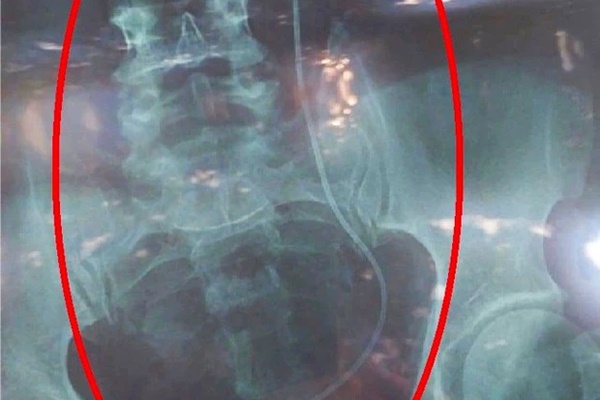

Tại Bệnh viện Nhi Đồng 2, sau khi thăm khám, các bác sĩ nghi ngờ trẻ bị dị vật nên tiến hành nội soi kiểm tra. Kết quả cho thấy, trong vùng kín của bệnh nhi 4 tuổi có một mảnh bông gòn còn bệnh nhi 5 tuổi là viên pin điện tử.

Sau khi lấy dị vật ra ngoài, tình trạng sức khỏe bệnh nhi đã bình phục tốt. Đây là 2 trường hợp trong số hơn 30 trẻ được phát hiện có dị vật từ năm 2021 đến nay tại Bệnh viện Nhi Đồng 2.